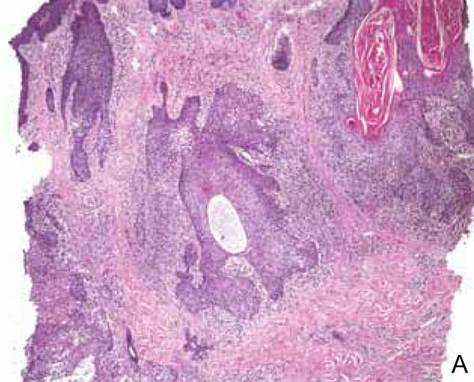

The characteristic histologic picture of LAFM in patch or plaque stage shows mucin deposition within hair follicles, similar to idiopathic FM. On histology, both conditions demonstrate dense lymphoid infiltrates around and within hair follicles as well as in the dermis (Figure). Most cases of LAFM show epidermotropism of lymphocytes between follicles, but this finding is not present in every case and often disappears when the disease advances to the tumor stage.1,19 Although Pautrier microabscesses (collections of lymphocytes within the superficial epidermis) are considered to be somewhat specific to MF, they are only present in a minority of cases.20 In a study by the International Society for Cutaneous Lymphomas,21 the only histopathologic criteria that showed any appreciable sensitivity or specificity in the diagnosis of MF were the presence of lymphoid cells with variable nuclear and cytoplasmic features and/or strikingly irregular nuclear contours with the presence of lymphocytes larger than those usually seen in inflammatory dermatoses. Despite these criteria, the study reported a high misclassification rate. A complicated scoring system for diagnosis of MF in patch- or early plaque-stage disease was proposed by the International Society for Cutaneous Lymphomas,21 which integrates clinical, histopathologic, molecular, and immunophenotypic criteria. However, these criteria have been continually debated in the literature and are only discussed in this article in relation to the association between MF and FM. Diagnosis of tumor-stage MF is not addressed in this article, as it is readily identified as lymphoma and is not easily confused with idiopathic FM.

Histopathology of 2 separate cases, both diagnosed as follicular mucinosis pending further follow-up. After close clinical follow-up, one case was diagnosed as mycosis fungoides (A) and the other as follicular mucinosis (B)(both H&E, original magnification ×2). Immunohistochemical stains were noncontributory, and T-cell gene rearrangement was positive only in the case of mycosis fungoides. Histopathology revealed mucin deposition in the hair follicles and a dense lymphoid infiltrate around and within the follicles in both cases. Pautrier microabscesses, cerebriform nuclei, and epidermotropism of lymphocytes between follicles were absent in the case of mycosis fungoides. |